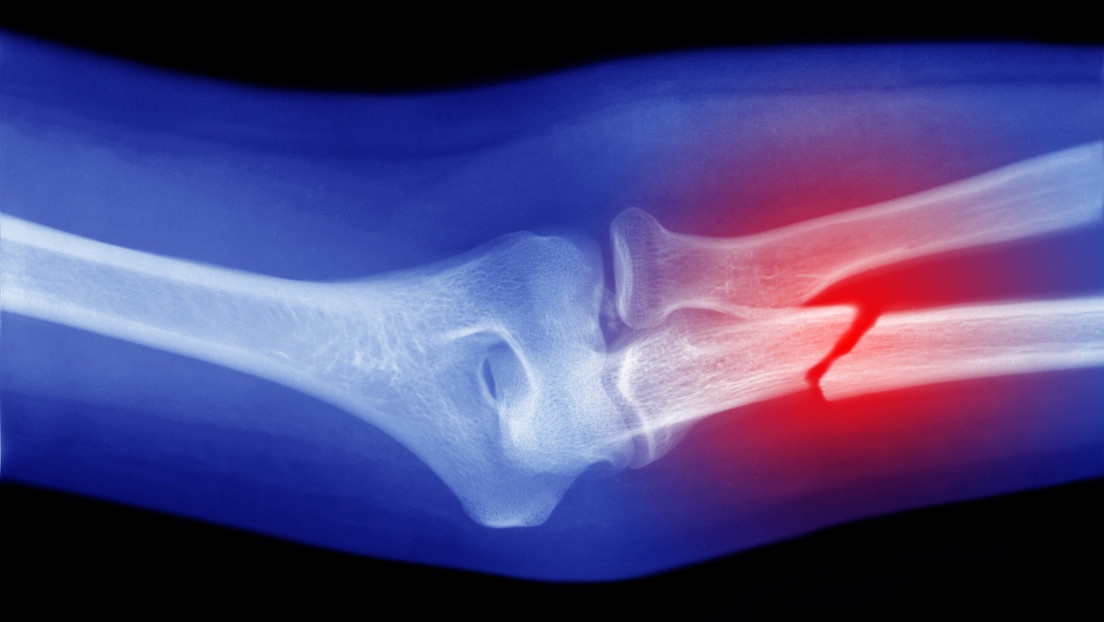

Moscú, 24 ago.- Científicos de la Facultad de Medicina Perelman de la Universidad de Pensilvania (EE.UU.) ha hecho un descubrimiento que podría facilitar la curación de fracturas, principalmente aquellas más complicadas.

Descubrieron que, tras una lesión ósea, migran al callo de fractura (estructura temporal que se forma para guiar la curación) y allí se transforman en células óseas. Finalmente, restablecen la superficie ósea, detalla su estudio, publicado en la revista científica PNAS.

De este modo, las Prg4+ podrían ser la clave para la curación ósea tras fracturas graves, cuando el hueso y la piel se rompen y se produce una pérdida extrema de tejido. Debido a que en estas heridas la reparación no siempre es eficiente, los científicos creen que, de cara al futuro, se podría estimular su actividad dentro del cuerpo o introducirlas de forma activada directamente en el lugar de la fractura para acelerar la curación ósea, señalan desde la Universidad de Pensilvania.